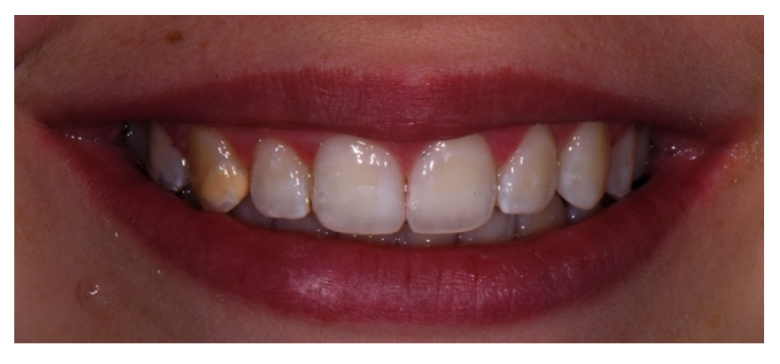

Terminata la terapia in office rileviamo per la seconda volta il colore dei denti trattati e confrontiamo i risultati con quelli iniziali (Fig. 3).

Dal confronto emerge che:

- l’incisivo 2.1 non mostra importanti cambiamenti di tonalità dentinale mantenendo un colore della scala Vita A1;

- l’incisivo 3.2 mostra un colore dentinale più uniforme rilevando una tonalità complessiva da C1 ad A1 con un miglioramento di 4 toni;

- il canino 1.3 si presenta più uniforme, passando da una tonalità A3,5 a D3 migliorando di 2 toni.